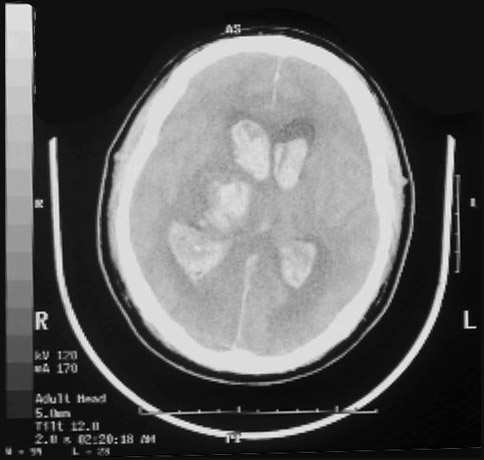

Click on the right thalamic hemorrhage in the radiograph above:

This is a computed tomographic (CT) scan demonstrating a hypertensive hemorrhage in the right thalamus that has extended into the ventricular system. Hemorrhages in this location are not amenable to surgical intervention with removal of the blood.